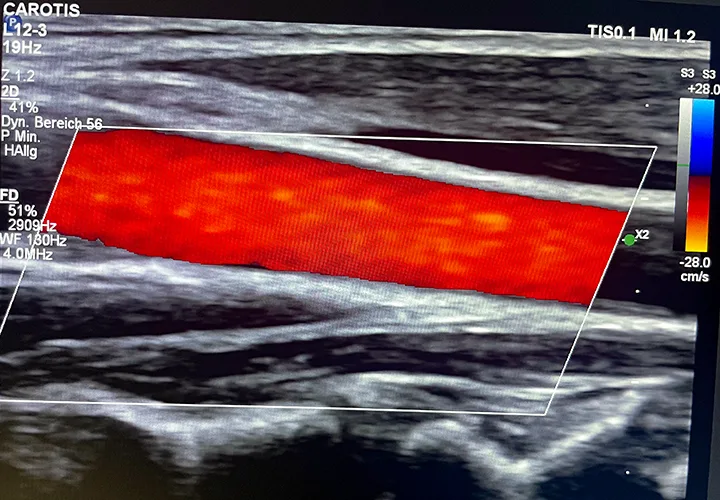

Gefäßdiagnostik

Karotis-Doppleruntersuchung

Früherkennung von Verengungen oder Verkalkungen der Halsschlagadern zur Einschätzung des Schlaganfallrisikos.